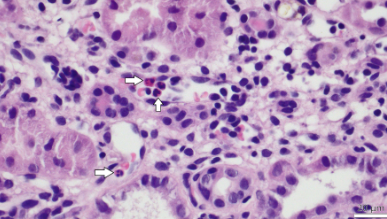

Under the microscope, the pathologist sees damage in various parts of the transplanted kidney and, on this basis, assesses the type of rejection we are dealing with. One type of rejection is microvascular inflammation. Until a few years ago, it was underestimated and overlooked. However, today we know that this pathological process, as part of the antibody-mediated rejection group, may be one of the causes of damage to the transplanted kidney. However, it is not easy to diagnose it non-invasively, i.e., without performing an organ biopsy.

Under a microscope, a transplanted kidney is very complex in structure. To someone unfamiliar with the histopathology of this organ, it may look like a city seen from a bird's-eye view. There are wide arteries—large vessels; smaller streets—capillaries; dense buildings—glomeruli; tubules. Various problems can arise in each of these areas.

If the process diagnosed by a pathologist in a kidney biopsy affects the glomeruli or capillaries, it is called microvascular inflammation (MVI). As a result of inflammation, the sensitive elements responsible for the proper functioning of the organ and blood filtration are damaged. Interestingly, until a few years ago, many cases that we now recognize as microvascular inflammation were not formally classified as rejection. Today, following the 2022 update of the Banff International Classification, which is the gold standard for histopathological diagnosis of transplanted kidneys, we know this is a severe warning sign, suggesting that something is wrong with the transplanted organ

The study, published in the journal Frontiers in Immunology, included 167 kidney transplant patients. What they all had in common was that they had undergone a biopsy in the past due to deterioration of transplant function. Pathologists evaluated these specimens according to the latest Banff 2022 criteria, looking for signs of microvascular inflammation. At the same time, blood samples were analyzed for the presence of AT1R antibodies.

How was Microvascular Inflammation (MVI) defined and diagnosed?

MVI was diagnosed histologically based on biopsy findings. According to the Banff Classification of Renal Allograft Pathology, MVI was defined by the presence of a glomerulitis score (g) > 0 and/or peritubular capillaritis score (ptc) > 0. The evaluations were based on the 2022 Banff Classification.